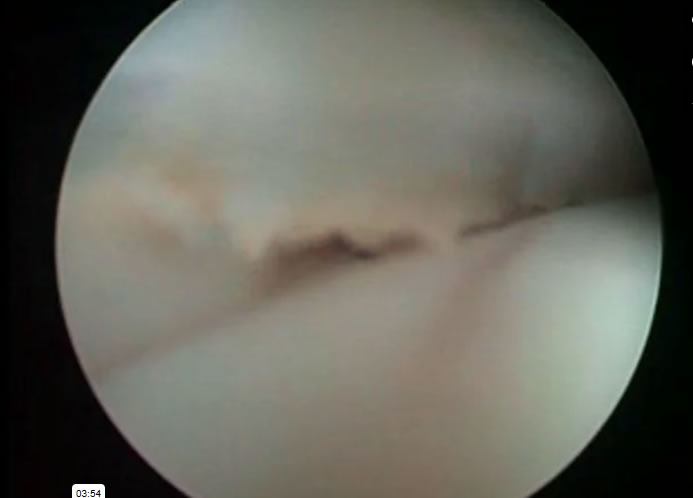

Medicos Cirujanos > Coloproctologos

Medicos Cirujanos > Endoscopistas